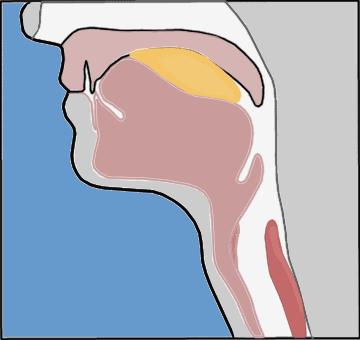

会厌是一个位于舌根后方的树叶状的结构,儿童为卷曲型,成年人多为阔叶型。就长在声门的上方,起到一个活瓣的功能,进食时会厌把声门盖严,食物和水就进入食道,避免呛咳窒息;敞开时气体可自由出入呼吸道,人就可以正常呼吸了。